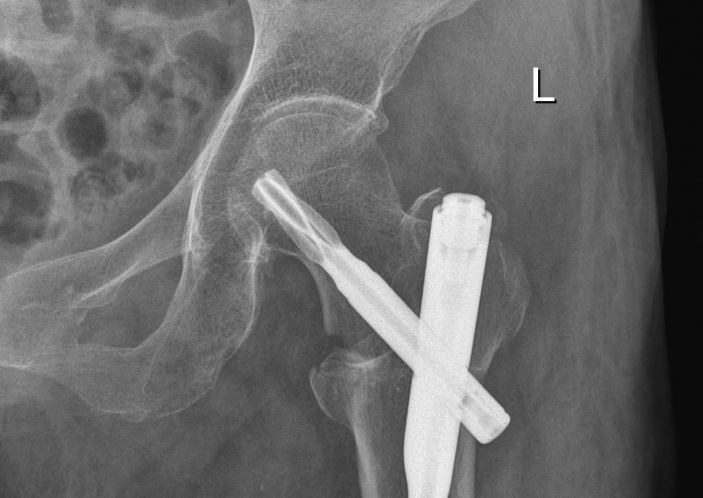

3月11日,康美醫院成功爲一名左股骨粗隆間粉碎性骨折的百歲老人開展股骨近端髓内釘(PFNA)内固定手術。

康美醫院外四科随即請内科、麻醉科等相關科室主任會診,經綜合評估,拟定詳細的治療方案。外四科吳主任決定盡早爲其開展微創手術治療,3月11日,在麻醉科和内科的配合下,吳主任帶領團隊成功爲黃婆婆施行左股骨粗隆間骨折閉合複位股骨近端髓内釘(PFNA)内固定手術,整個手術過程隻用了25分鍾左右,手術非常成功。術後醫護人員對其進行周密觀察、精心護理,患者恢複良好,已經康複出院。

據吳主任介紹,股骨近端髓内釘(PFNA)内固定手術屬于微創手術,具有手術切口小、創傷少、出血少、恢複快等優點。此次爲百歲高齡患者開展股骨微創手術體現我院外四科團隊的精湛技術,以及本院多科室配合綜合診治能力在本地區處于領先水平。